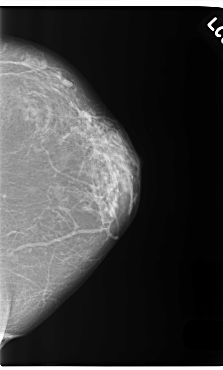

C_0255_1.LEFT_MLO

LEFT_MLO LINES 5880 PIXELS_PER_LINE 3624 BITS_PER_PIXEL 12 RESOLUTION 50 NON_OVERLAY